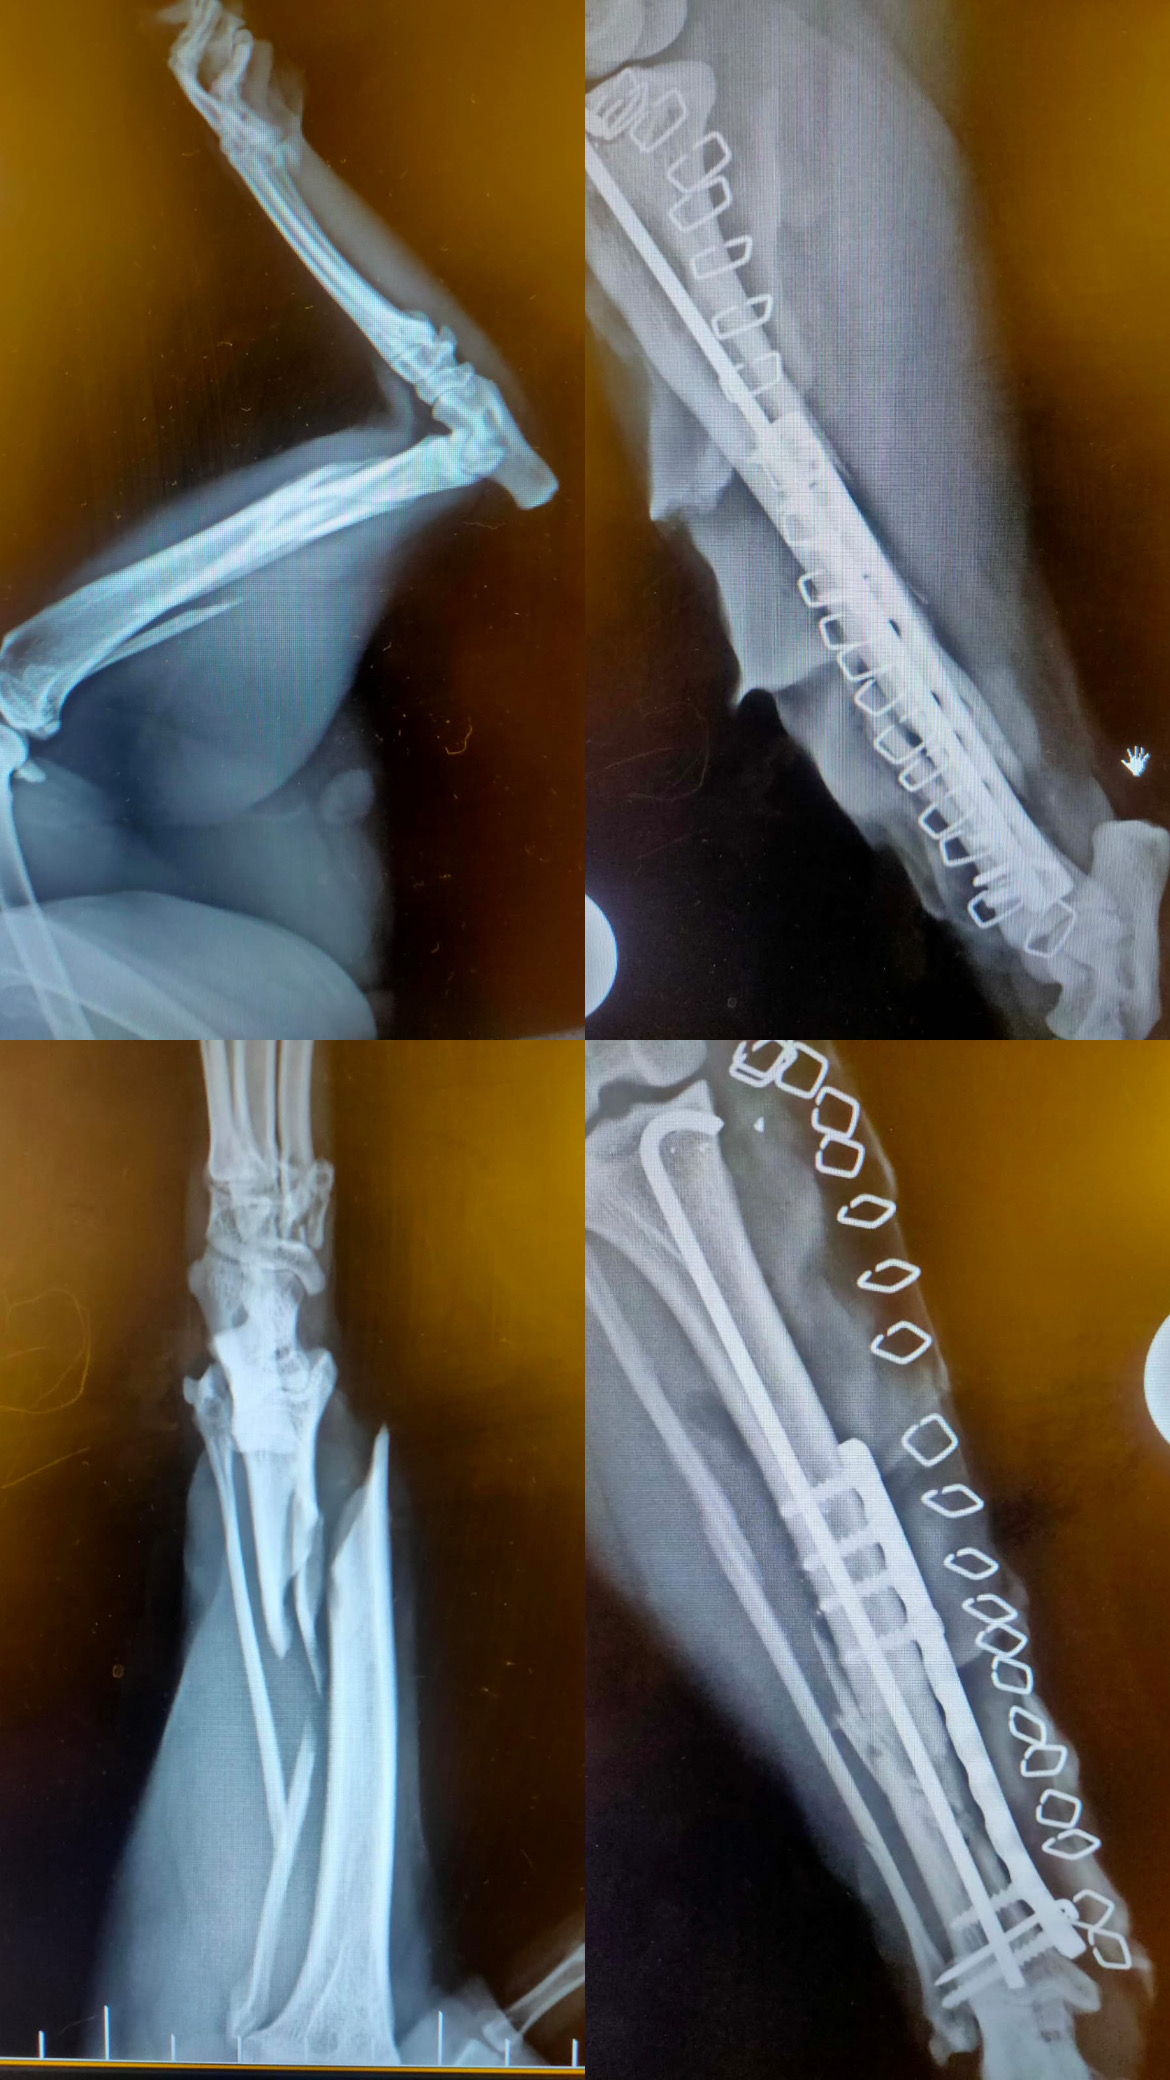

Pomozme Mannymu vstát a znovu chodit

Manny se propadl do sklepní šachty a následkem pádu si škaredě zlomil nohu. Musel podstoupit náročnou operaci a čeká ho dlouhá rekonvalescence.

V období těch nejhorších mrazů se snažil za každou cenu dostat do tepla domu, až spadl do sklepní šachty, z které by nikdy sám nevylezl, kdyby jsme ho nehledali. Zlomenina levé zadní nožky je šílená a Manny si vlastně vydobyl to, že už se na krmné místo nikdy nevrátí, protože nožka je nenávratně poškozená. Operaci podstoupil v Hradci Králové, kde nám vystavili předběžnou kalkulaci a čekají nás ještě měsíce rehabilitace. Bohužel pro naše depozitum jsou tyto částky za operace naprosto fatální a ohrožují celý chod útulku. Sami to prostě nezvládneme, budeme rádi, když Mannymu pomůžete. Měl by vědět, že ne všichni lidé jsou bezohlední a že i on, obyčejný kocour si zaslouží žít.